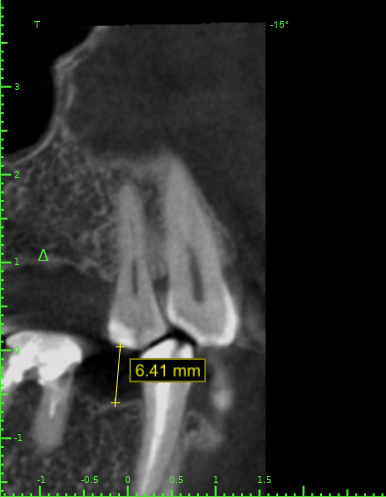

annda Опубликовано 17 декабря, 2021 Поделиться Опубликовано 17 декабря, 2021 (изменено) Тут весь прикус поднимать надо, с заменой протетики слева и восстановлением стертых резцов и клыков , а вы про инвазию на премоляре:)) Изменено 17 декабря, 2021 пользователем annda 1 Ссылка на комментарий

Женька Опубликовано 17 декабря, 2021 Автор Поделиться Опубликовано 17 декабря, 2021 @annda опасно туда лезть... ибо на этапе протезирования в другой клинике там что-то шаманили долго и пациентка длительное время испытывала дискомфорт (то щель большая, то вообще её нет, то нависающие края и гингивит) Ссылка на комментарий

annda Опубликовано 17 декабря, 2021 Поделиться Опубликовано 17 декабря, 2021 Если она на этапе протезирования в другой клинике, то зачем вы там с интрузиями и обрезаниями? Ссылка на комментарий

annda Опубликовано 18 декабря, 2021 Поделиться Опубликовано 18 декабря, 2021 (изменено) Пардон, недопоняла, что она уже закончила этап протезирования в другой клинике. И теперь начинает у вас. Но ее рассказы о дискомфорте и прочих субъективных неприятностях не отменяют объективной картины во рту. Я про снижение VDO и, патологическую стираемость зубов, повышенный тонус жевательных мышц и сопутствующие возможные проблемы с суставами ,и прочие постуральные радости. Ортопед то хоть мельком обследовал на этот счет ее? В результате, главное, чтобы она об этом знала и дала согласие на лечение или подписала отказ от медвмешательства. Когда начнет испытывать дискомфорт уже после вас, чтобы можно было к чему аппелировать и прикрыть свою пятую точку. Изменено 18 декабря, 2021 пользователем annda Ссылка на комментарий